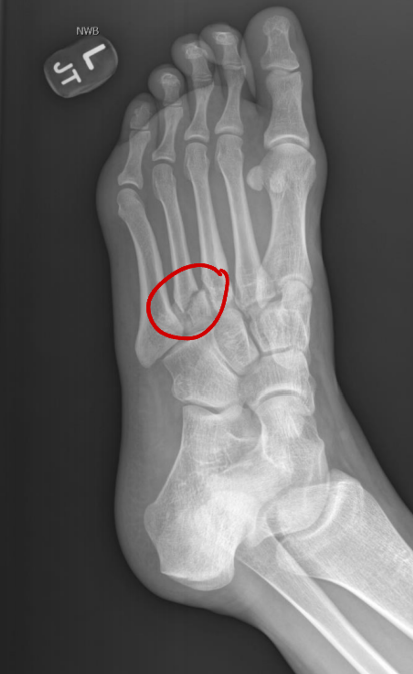

<p>What is wrong with this patient?</p>

What is wrong with this patient?

Nothing, this is a pediatric radiograph. The lines show epiphyseal plates